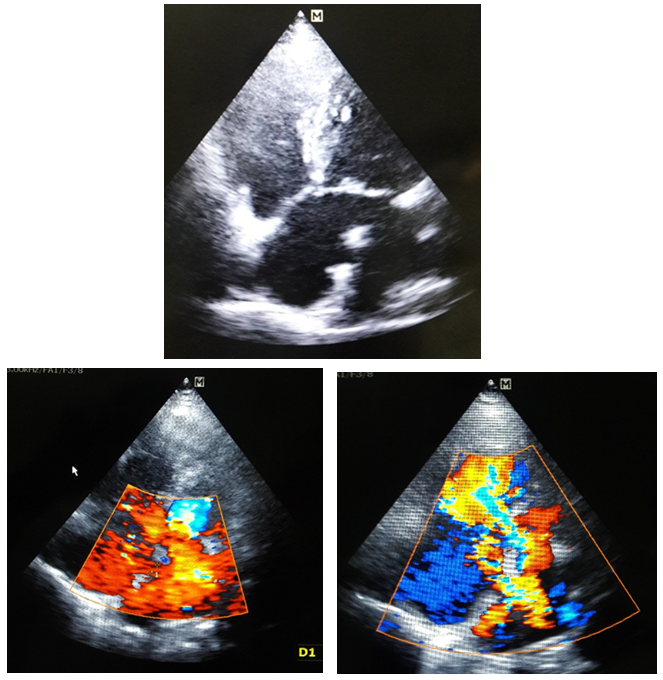

An Unusual Atrial Septal Defect Producing Symptoms in a Young Lady

Md. Mashiul Alam, Md. Al-Amin

International Journal of Innovative Research in Medical Science·February 4, 2020